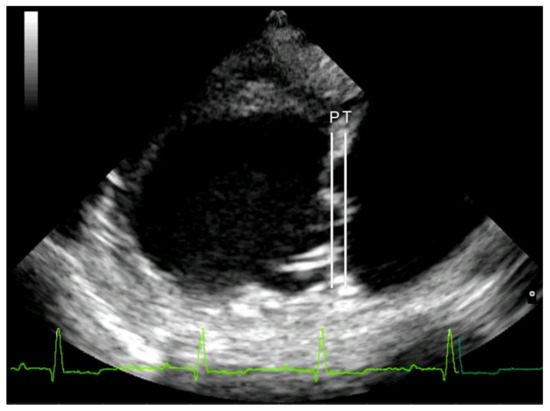

Mitral valve prolapse was considered mild if the leaflets were prolapsing but did not cross the line joining their pivotal points (line P), moderate if they protruded between the P line and the line joining half of the echoic areas located in the lower part of the atrial septum at the level of atrioventricular junction (T line), and severe if the leaflets exceeded the T line [29] (Figure 1). Lastly, MR was assessed by color Doppler, calculating the maximal ratio of the regurgitant jet area signal (ARJ) to the left atrium area (LAA) (ARJ/LAA ratio) in left parasternal long-axis view [24].

Figure 1. Right parasternal long-axis four-chamber view of a Cavalier King Charles Spaniel (CKCS) affected by myxomatous mitral valve disease (MMVD) in American College of Veterinary Internal Medicine (ACVIM) class D; severe mitral valve prolapse was assessed by the protrusion of one or both leaflets over line T. The arrows outline the severity of mitral valve prolapse and the affected leaflet. Line P is drawn from the hinge point of the anterior leaflet to the hinge point of the posterior leaflet. Line T is drawn from the middle of the elliptical echogenic area at the lower part of the atrial septum to the atrioventricular junction, i.e., the junction between the left ventricular wall/annulus fibrosis and the left atrial wall.